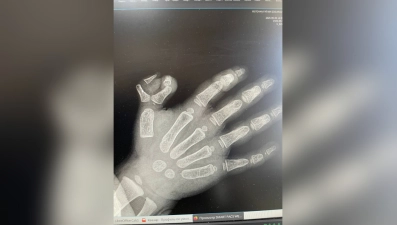

Елецкие травматологи прооперировали маленькую девочку с полидактилией правой кисти – у неё было шесть пальцев на руке.

Поскольку ребёнок является правшой, деформация кисти особенно осложняла ей жизнь. Хирурги успешно удалили девочке проблемный палец.